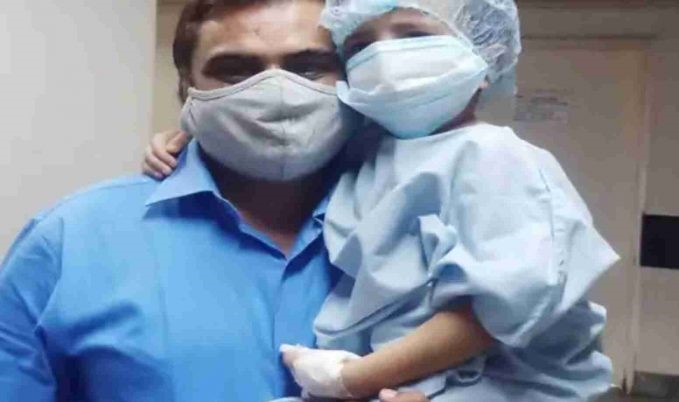

એક્સ-રે માં બાળકના પેટમાં ચુંબક દેખાયું હતું. ત્યારબાદ ઘરના લોકો બાળકને તેના પેટમાંથી ચુંબક કાઢવા માટે અરિહંત હોસ્પિટલ લઈ ગયા હતા. હોસ્પિટલ મેનેજમેન્ટે એન્ડોસ્કોપીમાંથી મેગ્નેટ કાઢવાનું કહ્યું. પરંતુ તે દિવસે એનેસ્થેસિયાના નિષ્ણાતના અભાવે તેને બીજા દિવસે આવવાનું કહેવામાં આવ્યું હતું. જયારે બીજા દિવસે જ્યારે બાળકના પેટમાંથી ચુંબક કાઢવા લાગ્યા ત્યારે બાળકનું મૃત્યુ થયું.

કબીરના પિતા સુનીલ તિવારીએ જણાવ્યું કે ચુંબક ગળી ગયા પછી કબીરને ઉધરસ અને તાવ આવ્યો હતો. તો ડોક્ટરોએ કહ્યું કે જયારે સારું થઈ જશે પછી તેના શરીરમાંથી ચુંબક દૂર કરવામાં આવશે. આ પછી, મંગળવાર બાળકની એન્ડોસ્કોપી કરવામાં આવી અને તે પછી તેને બેભાન કરવા માટે એનેસ્થેસિયા આપવામાં આવ્યું.

ડોક્ટરોએ બાળકના પેટમાંથી એક ચુંબક પણ બતાવ્યું અને કહ્યું કે બાળક અડધા કલાકમાં ચેતના પાછી મેળવી લેશે. પરંતુ લગભગ અઢી કલાક બાદ ડોક્ટરોએ જણાવ્યું કે બાળકનું મોત થયું છે. પરિવારે આરોપ લગાવ્યો કે બાળકનું મોત એનેસ્થેસિયાના ઓવરડોઝને કારણે થયું છે. પરિવાર માટે આ સમગ્ર ઘટના માટે હોસ્પિટલ મેનેજમેન્ટ અને ડો.સોનલ નિવસરકર જવાબદાર ગણાવ્યા છે.